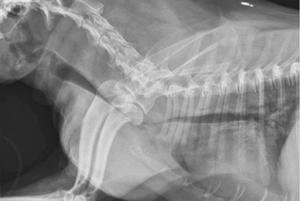

Методы диагностики

Так как клиническая симптоматика может развиваться в единичных случаях, а в основном слабо либо долгое время вовсе не показывать себя, то подтверждение диагноза «коллапс трахеи» всегда требует осуществления более тщательного осмотра с использованием нового оборудования.

Для начала стоит провести пальпацию трахеи собаки. Если болезнь всё-таки имеется, то форма трахеи очень сильно деформирована — на стенке в это время образуется жёлоб либо же сильное уплотнение.

Диагностика у животного может быть затруднённой. Держать питомца на одном месте и поймать время его вдоха-выдоха в большинстве случаев очень сложно. В некоторых случаях собака нуждается во введении успокоительного средства и бариевой кашицы, лишь таким способом она приходит в себя и становится спокойнее. Иногда осуществляют забор ткани трахеи для определения возбудителя болезни и анализа крови на чувствительность к препаратам-антибиотикам.

Время от времени стоит привозить собаку в ветеринарную клинику на эндоскопию и рентгенологическое обследование, чтобы внимательно следить за имплантом или стентом.

Диагностика коллапса трахеи обычно включает физический осмотр ветеринаром, прослушивание дыхательных звуков и рентгенографию грудной клетки. В некоторых случаях может потребоваться бронхоскопия для визуализации трахеи и оценки степени коллапса.